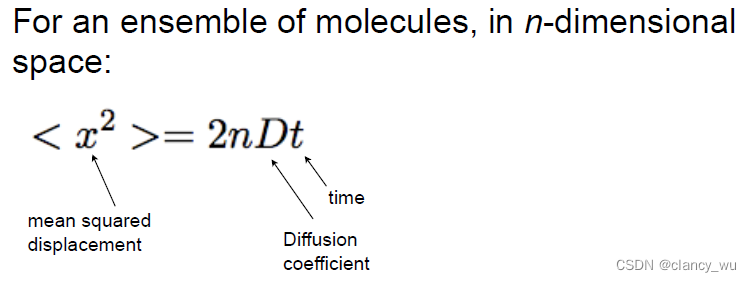

大家都知道,分子处于不断的随机运动中,这种运动被称为布朗运动,也讲作弥散(diffussion)。

Diffusion = thermally-driven random motion

如何描述这种弥散呢?爱因斯坦提出了下述公式:

这种现象在大脑里也是存在的,因为大脑传递信息是通过神经元,而神经元的结构是树突和轴突组成,轴突就是方向性的连接。

在纤维束中,分子的扩散是各向异性的(anisotropic),水和液体和灰质是各向同性的(isotropic)。这很好理解,简单说就是纤维束中的分子运动只能朝着纤维束的方向扩散(轴突),脑脊液中的分子运动可以朝着周围随意运动,向各个方向运动的概率是相同的,这就是各项异性和各项同性的简单理解。这个是DTI分析的基本知识和背景。

所以其实纤维束构建的本质就是通过数学方法来计算Diffusion。说到计算,核磁里有一个技术,Pulsed-Gradient Spin-Echo Sequence(脉冲梯度自旋回波序列),就是在时间t内施加一个x方向的强磁场梯度,观察分子在前后运动的距离,就可以得出来弥散速度。